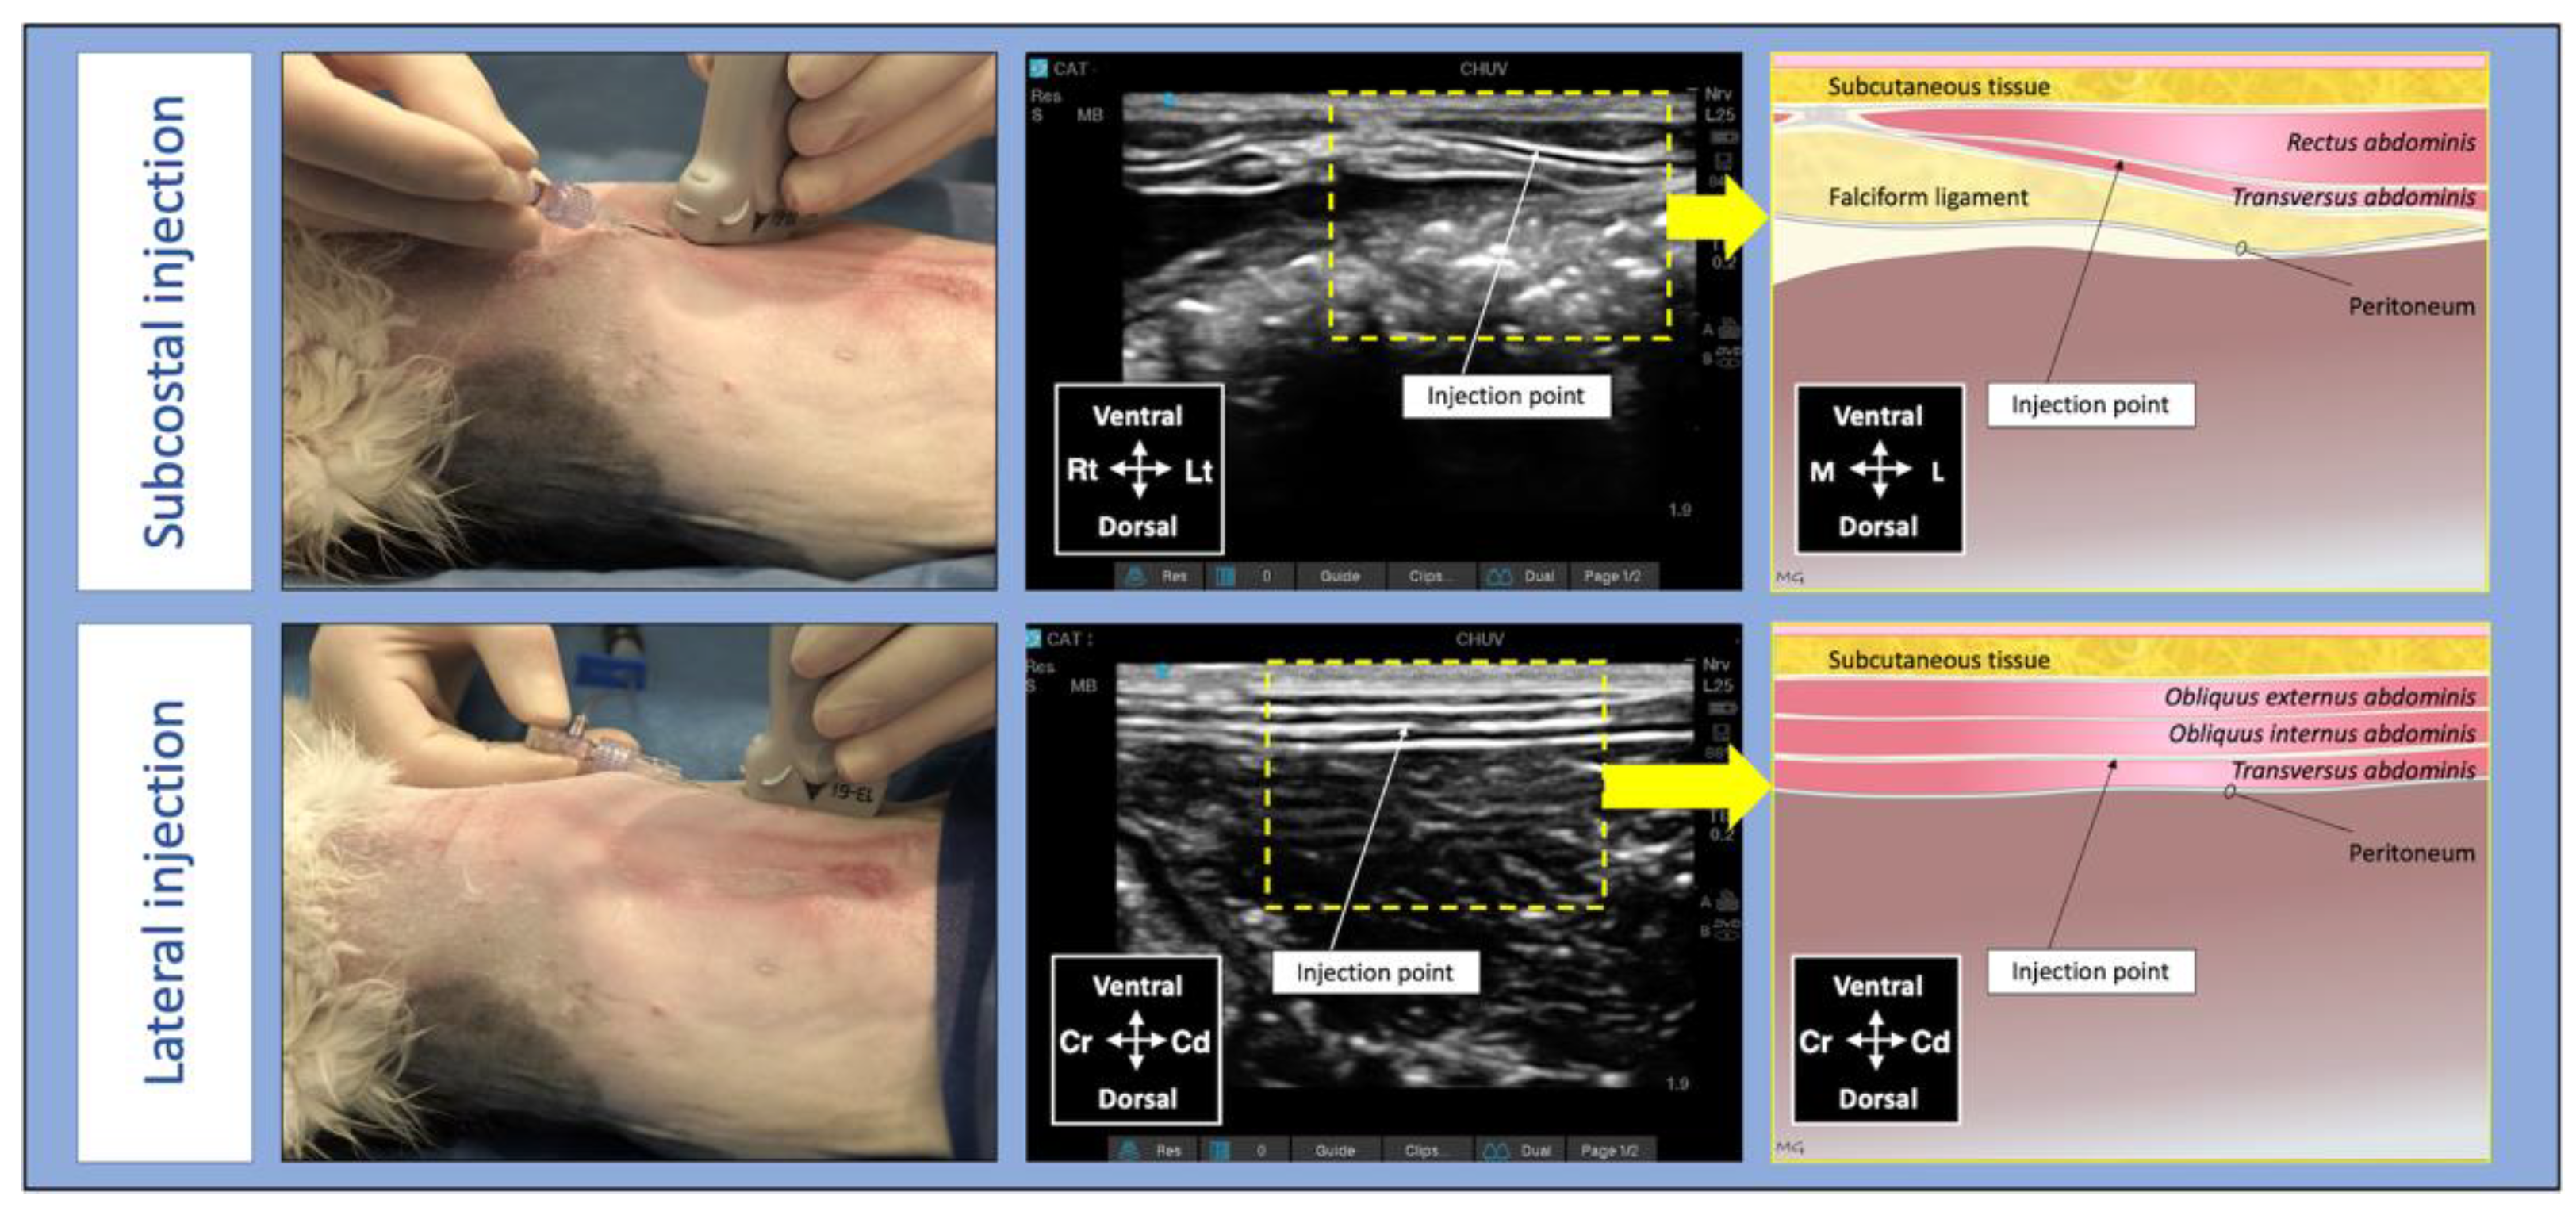

2.1.3. Anaesthesia and Surgery